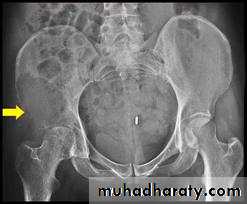

For bone metastases are thecommonest sites

Vertebrae,pelvis,

proximal half of the femur and

humerus.

Metastases are usually osteolytic,

and pathological fractures are common.Bone resorption is due either to the direct action of tumour cells or to tumour-derived factors that stimulate osteoclastic activity.

Osteoblastic lesions are uncommon; they usually occur in prostatic carcinoma.

Most skeletal deposits are osteolytic and appear as rarified areas in the medullaor

produce a moth-eaten appearance in the cortex.

sometimes there is marked bone destruction, with or without a pathological fracture.

Osteoblastic deposits suggest a prostatic carcinoma; the pelvis may show a mottled increase in density which has to be distinguished from

Paget’s disease

Or

lymphoma.